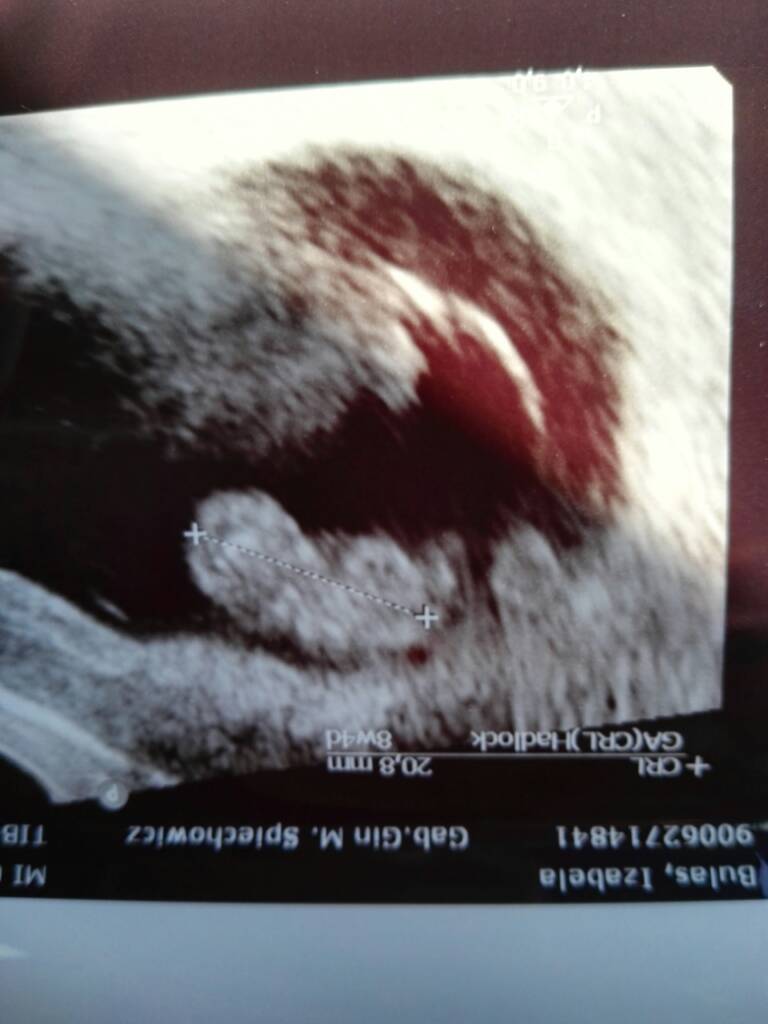

Moje 2cm szczescia [emoji4] serduszko bije 178 razy na minute [emoji4] Poplakalam sie na usg jak zobaczylam ze wszystko jest i dzidzius i serduszko [emoji7]